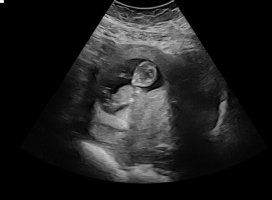

Syns dette ser veldig ut som en gutt, pga det «laget» oppå + at den går oppover. Men har du noen flere bilder?13+2 noen som har en tanke her? Synst selv nubben her er mye flatere enn med gutten jeg har

Usikker på om det er nub man ser?13+2 noen som har en tanke her? Synst selv nubben her er mye flatere enn med gutten jeg har

Jeg spurte flere sider, men ene sa at de ikke ville si noe da bare en liten del av Nuben visste så det var vanskelig å si noe om kjønn..Usikker på om det er nub man ser?

Dette er kanskje Nuben?Usikker på om det er nub man ser?

Du hadde rett! Det var navlestrengen. Ingen nub på bildet.Usikker på om det er nub man ser?